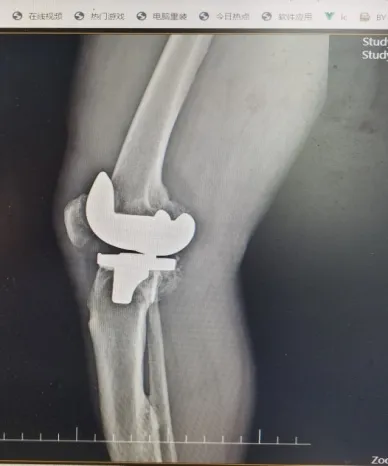

何爷爷在梓潼县人民医院骨科接受了人工全膝关节置换术,术后他的疼痛显著缓解,关节功能逐步恢复。术后当天在康复师的专业指导下,逐步开展膝关节功能锻炼,以促进血液循环和防止血栓形成。术后第2天,何爷爷便能在医护人员陪同指导下使用助行器下床活动。

人工全膝关节置换术

人工全膝关节置换术适用于主要由膝关节病变导致关节疼痛、功能障碍和畸形的患者,包括骨关节炎、类风湿关节炎、创伤性关节炎、血友病性关节炎等关节疾病。通过进行人工全膝关节置换术以及术后积极的功能锻炼,可以帮助患者减轻关节疼痛,改善关节功能,矫治关节畸形,进而提高生活质量。